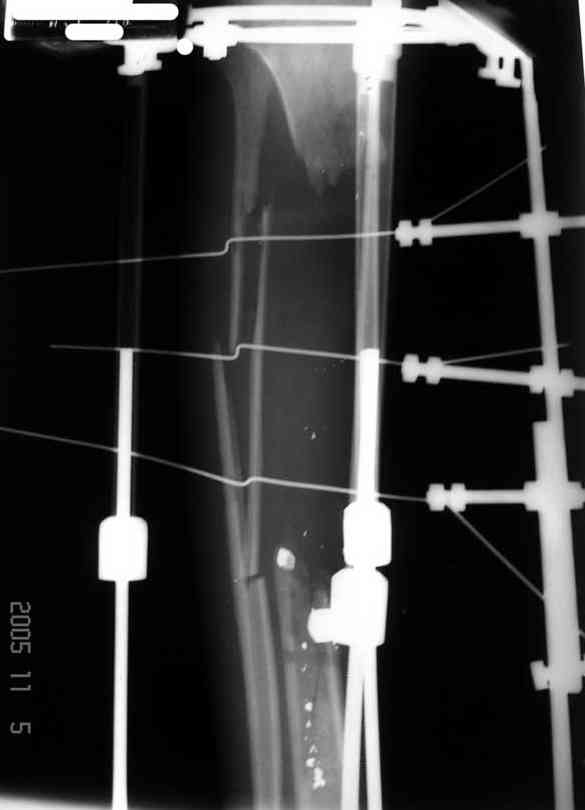

5. Ну и чтобы не быть голословным. Молодой человек подорвался на фугасе (Чечня, 2005 год). Свежие рентгенограммы:

Соответственно ожоги и дефект мягких тканей, переломы костей стопы и пр. Наложили аппарат

Илизарова (как придется), хирургически обработали и героически заживляли мягкие ткани с многочисленными кожными пластиками. В итоге через полгода я принял его вот таким:

Реализовал описанную выше методику, и в итоге вот что получилось. Высылаю лишь прямые проекции,

в боковых тоже всё в тему.

Очень пригодились карбоновые кольца (Джолдас -огромное спасибо, я твой должник!!!), поскольку остеопороз дистального отломка был просто невероятный. На цифровом рентгене с трудом угадывались контуры.

Рентген в процессе перемещения - внизу карбоновые кольца, тракция фрагмента спицами с упором.

внешний вид в аппарате - не завершающем этапе, сначала стопа тоже была фиксирована в аппарате.

Сейчас аппарат сняли, но случай ещё не завершенный.

Признаюсь честно, не совсем уверен в прочности консолидации на стыке косточек. Кроме того, укорочение в районе 6 см. Сейчас реабилитация - ходит опираясь на ногу с одним костылем.

Продолжение, видимо, будет... Возможно, будем удлинять.